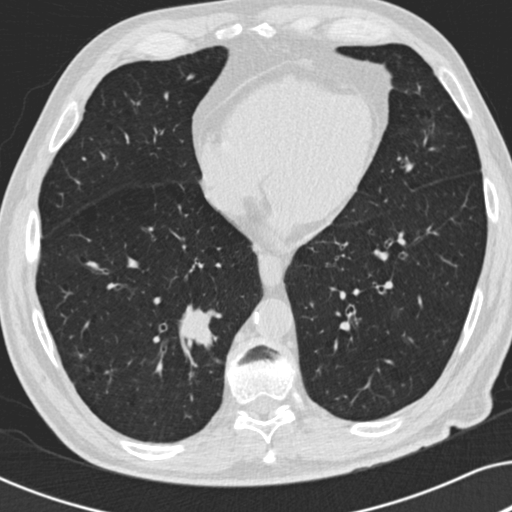

Choose if image shown above is Real or Fake :

Real

Fake